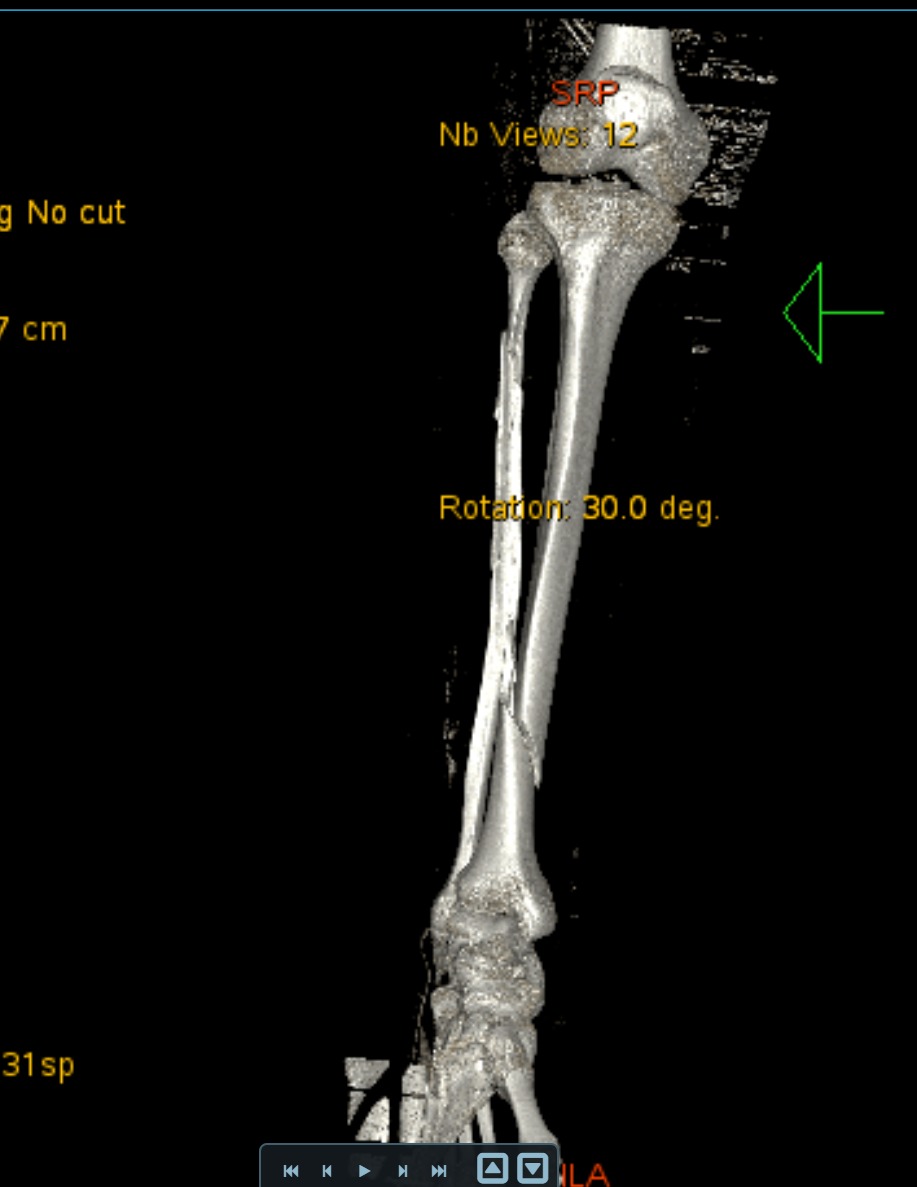

Bij deze mijn ervaring van 9 okt 2025

Ik zou je eerder een e-fiets van 25km/u aanraden, ideal compromis tussen veilgiheid, afstand en prijs.

Als ervaren motard die geregeld laagvliegt met race machientjes... Ik heb nu bang op een speed pedelec